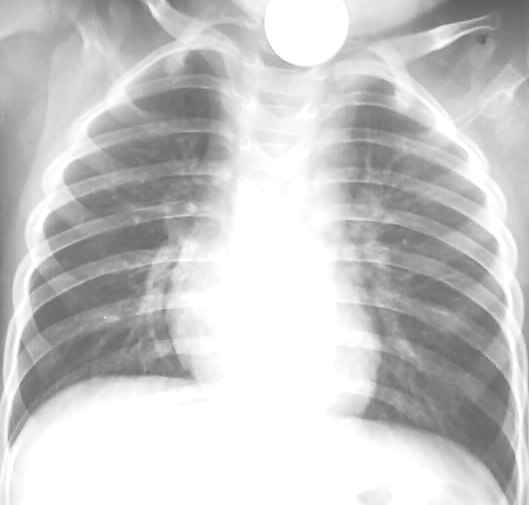

以下是引用随光逐影在2009-4-12 16:07:00的发言:[br]两肺尚清晰,心膈正常。[br]颈部体外异物?

以下是引用yrj0513在2009-4-12 18:42:00的发言:[br]结果:气管内异物(硬币),发帖的目的,是让战友们注意此问题.